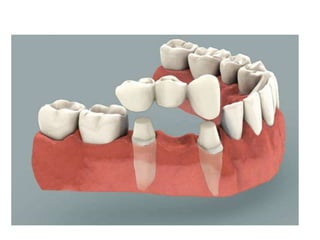

Bridge: (fixed prosthesis)

(fixed partial denture): is a non

movable prosthesis which is

rigidly attached to one or more

abutment teeth to replace one or

more lost missing teeth.

Component Parts of bridge

Abutment tooth Retainer

Pontic

Connector

* Abutment tooth: is the

natural tooth which supports

* Pontic: is that part of the

bridge which act the actual

substitute for the lost tooth and

is suspended between the

retainers replacing the lost

natural tooth functionally and

esthetically.

* Retainer: The artificial

restoration rebuilding

prepared abutment tooth

and by which the pontic is

attached to the abutment.

* Connector: is that part of the

bridge uniting the pontic (s) with the

retainer(s), so that to join the component

parts of the bridge.